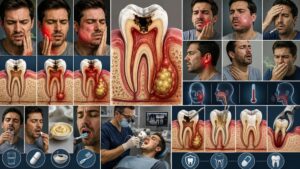

Some common Issues detected by 3D imaging

- Tooth Decay and Cavities: 3D scans can identify cavities that are not visible on regular X-rays, including those between teeth or below fillings.

- Root Canal Issues: 3D imaging helps detect abscesses, infections, or cracks in the root of the teeth that may require root canal treatment.

- Jawbone Loss or Damage: 3D scans can reveal bone loss or abnormalities in the jaw, which are critical for planning dental implants or other surgeries.

- TMJ Disorders: Issues related to the temporomandibular joint (TMJ), such as misalignment or damage, can be clearly seen in 3D imaging.

- Misalignment of Teeth and Bite Problems: 3D imaging allows dentists to assess how teeth and jaws align, helping detect bite issues or misalignments that may require orthodontic treatment.

- Sleep Apnea and Airway Obstructions: 3D imaging can pinpoint structural issues in the jaw and airway that contribute to sleep apnea or breathing difficulties.

- Cyst and Tumor Detection: Cysts, tumors, or other abnormal growths in the mouth or jaw can be identified early using 3D imaging.

- Dental Implant Planning: Accurate 3D scans help dentists plan for dental implants by showing bone density and the best placement location.